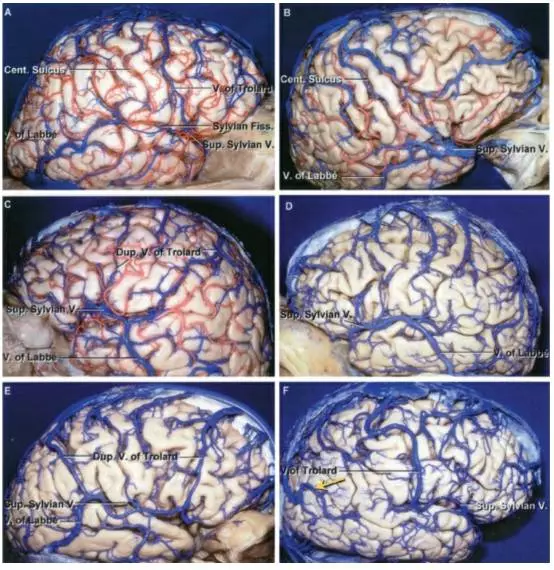

图4. 顶上小叶附近的静脉解剖和变异特点。尽管该区域的矢状窦旁静脉比较稀少,一些大脑半球上仍然会有不能牺牲的Trolard静脉复制体(E)。此外,在顶上小叶前方和后方往往会有粗大的引流静脉,尤其是在Labbe静脉缺失的情况下(黄箭头,F)(插图来自AL Rhoton,Jr)。